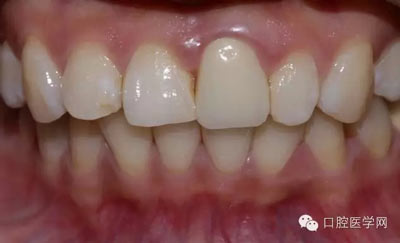

術(shù)前照

檢查:21金屬烤瓷冠修復(fù),顏色及形態(tài)與鄰牙不協(xié)調(diào),牙齦有輕微發(fā)黑,扣痛(-)、松動(dòng)度(-);11近中鄰面齲壞